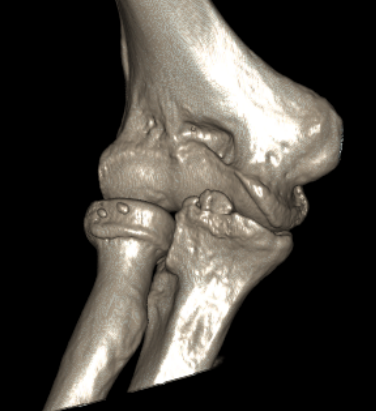

CT

Define olecranon and coranoid process osteophytes

Identification loose bodies

Osteophyte of the olecranon likely impinging in extension

CT demonstrating loose bodies in the ulnohumeral joint

Multiple loose bodies in anterior and posterior elbow joint